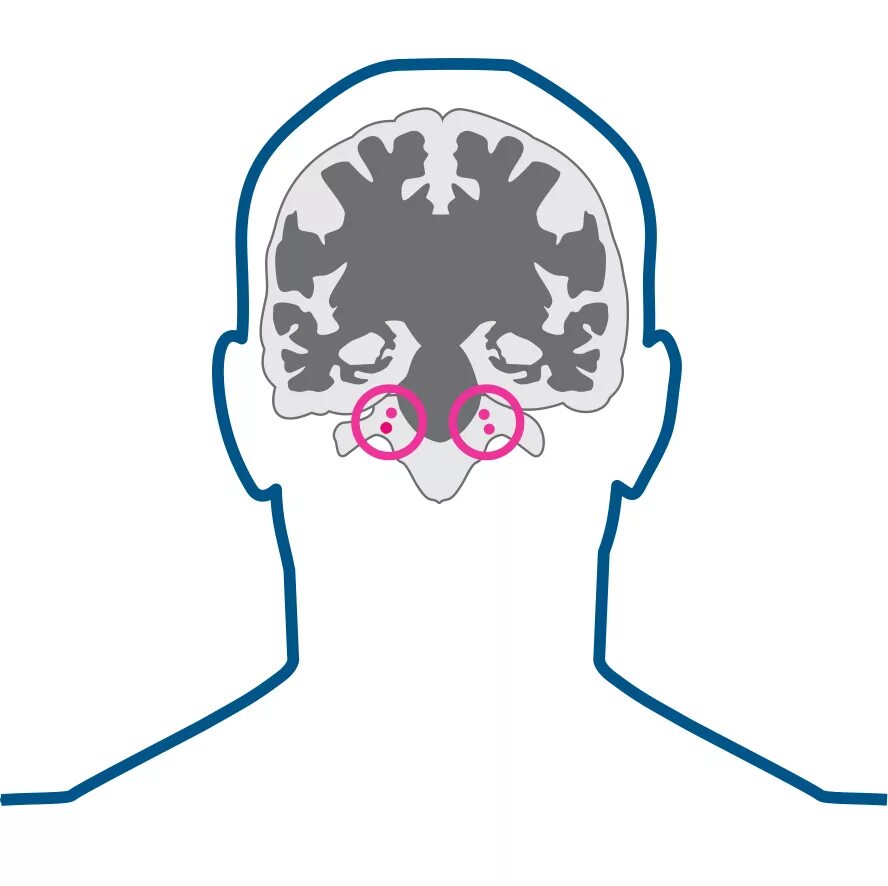

Нейроваскулярный конфликт нерва